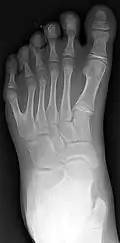

X-ray of type III central polydactyly (the middle fingers are the same length).

Classification is performed by using x-ray imaging to see the bone structures.[19]